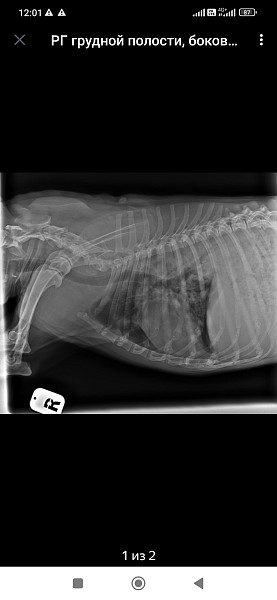

Добрый день!собачка кобель цвергпинчер 14 лет 10 месяцев,стал часто дышать,сделали рентген,помогите понять что с ним!

Ренген

Добрый день!ренген лёгких у собаки помогите прояснить ситуацию!сделали в связи с частым дыханием

Здравствуйте, у собаки выраженное затемнение по каудальным долям легких. Более всего это похоже на пневмонию.